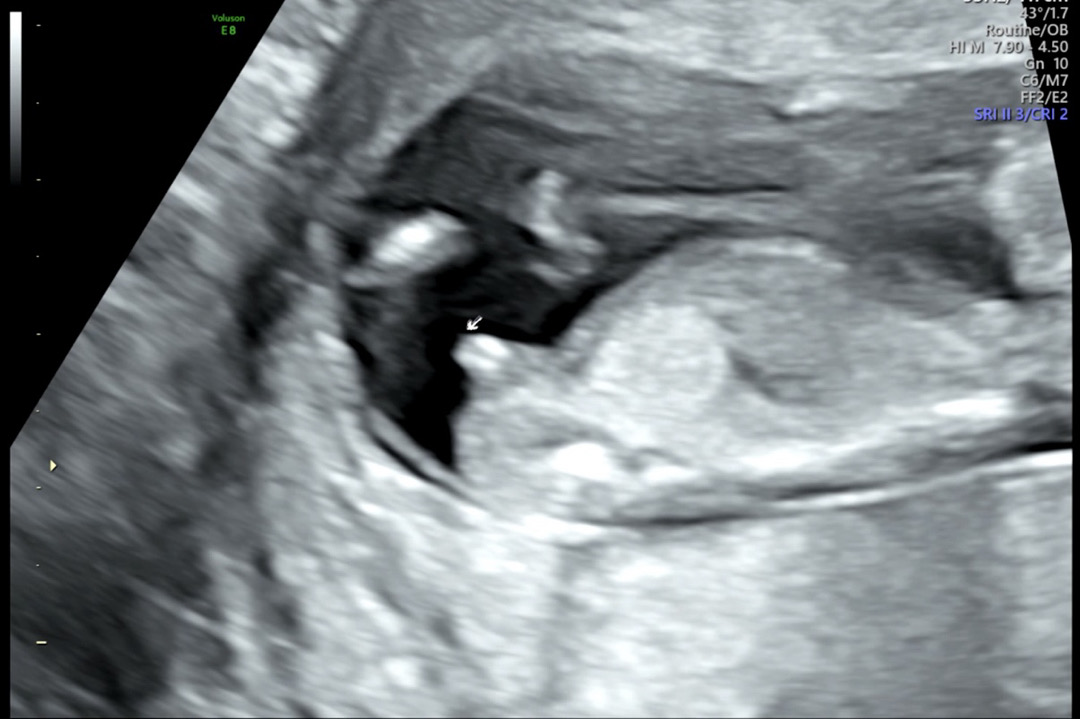

12+1 일 각도법 봐주세요

12주사진이에요